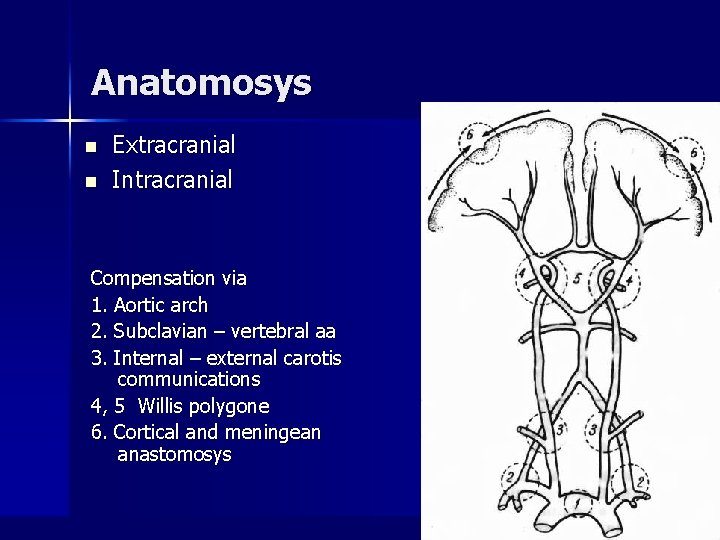

Anatomosys n n Extracranial Intracranial Compensation via 1. Aortic arch 2. Subclavian – vertebral aa 3. Internal – external carotis communications 4, 5 Willis polygone 6. Cortical and meningean anastomosys